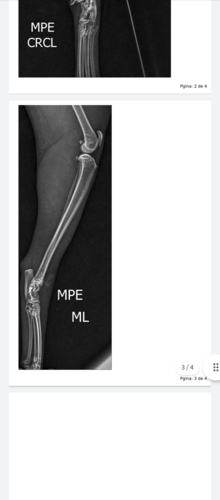

Meus amigos sei que as vezes não temos como ajudar o próximo mais venho pedir ajuda minha gatinha foi machucada por alguém que não tem amor ao próximo ela está o uma das patas traseira quebrada e eu não tenho condições para custear a cirurgia dela no momento se você puder me ajudar eu ficarei grato ou se puder compartilhar com alguém que ajude também ficarei grato por ajuda nessa corrente eu agradeço muito pela atenção de cada um de vocês obrigado e Deus abençoe sua vida…